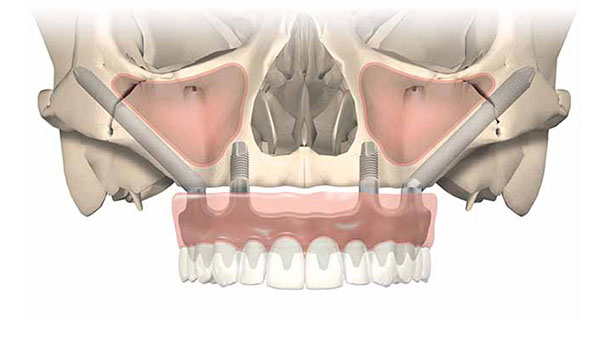

4. Zygomatic Implants

All-on-4/ All-on-6 and zygoma implants are immediate function and graftless solution implants. The implant concept tilts posterior implants to maximum jaw bone volume on the anterior area. Where there is insufficient bone, long zygomatic implants may be placed to hold a fixed hybrid denture in place.